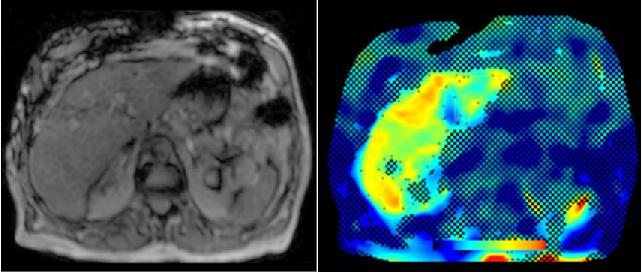

Abdominal MR Imaging

Michaela Plaikner, Benjamin Henninger, Christian Kremser

Morphological and functional MRI in all-organ systems development of novel MRI applications and MR sequences. Examples of research projects: fat, iron or combined disease; influence of iron on the evaluation of liver fat.

a) MRI for the evaluation of diffuse liver disease:

evaluation of different MRI methods (relaxometry, chemical shift imaging, multi-echo approach, Dixon screening), in order to detect diffuse liver disease (fat, iron or combined disease); influence of iron on the evaluation of liver fat.

b) MR-Elastography (MRE)

MRE is increasingly used in hepatic MRI to detect and classify fibrosis in the early stages before morphological changes have occurred. In our department, MRE is already integrated into the routine hepatic MRI protocol and used for various research projects.